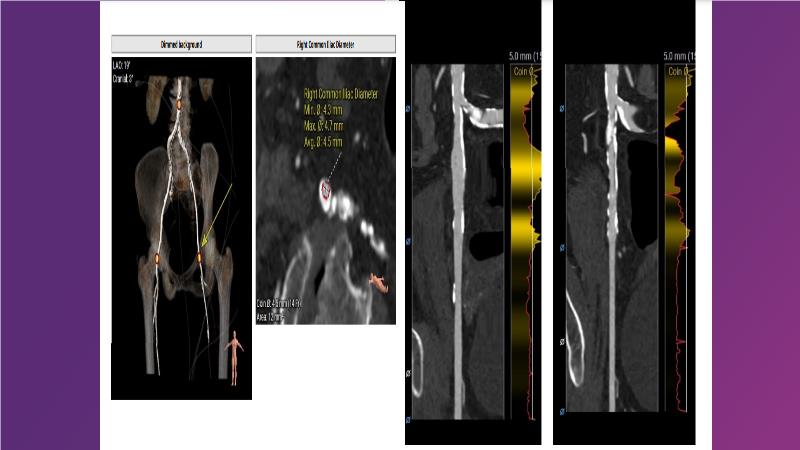

• To learn how to select your TAVI device in order to achieve stable deployment in 90 degrees horizontal aorta

• To witness smooth deliverabilty even crossing tight and tortous anatomy